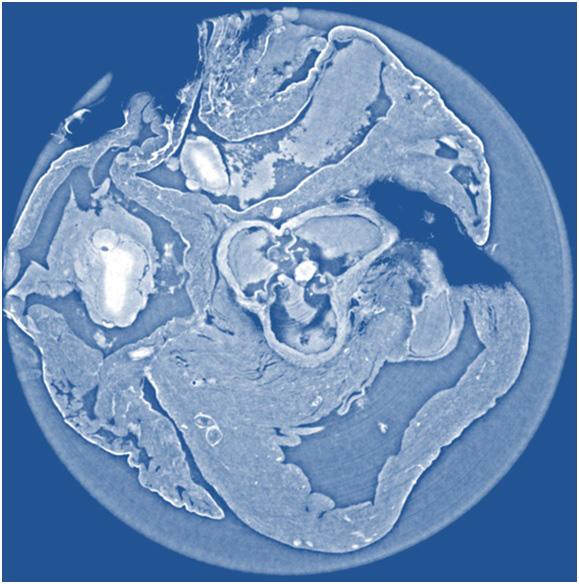

WASHINGTON, D.C., October 21, 2014 -- X-ray phase tomography is an imaging technique that uses penetrating X-rays to create volumetric views through "slices" or sections of soft biological tissues, such as tumors, and it offers strongly enhanced contrast compared to conventional CT scans. Yet scientists still do not know which X-ray phase tomography methods are best suited to yield optimized results for a wide variety of conditions.

To answer this question, a large group of researchers in Europe set out to compare three different X-ray phase tomography methods at the European Synchrotron Radiation Facility's (ESRF) beamline ID19 in France—X-ray grating interferometry, propagation-based phase tomography with single-distance phase reconstruction, and holotomography.

Led by Irene Zanette, a scientist affiliated with both ESRF and the Technische Universität München (TUM) in Germany, the researchers put these three techniques to the test by examining cancerous tissue from a mouse model and an entire rat's heart, which they report this week in the Journal of Applied Physics , from AIP Publishing.

So what did they find by comparing methods? The group was able to show that for each specimen, the spatial resolution derived from the characteristic morphological features is about twice as good for holotomography and single-distance phase reconstruction compared to X-ray grating interferometry. They also found that X-ray grating interferometry data generally provide much better contrast-to-noise ratios for anatomical features, excel in fidelity of the density measurements, and are more robust against low-frequency artifacts than holotomography.